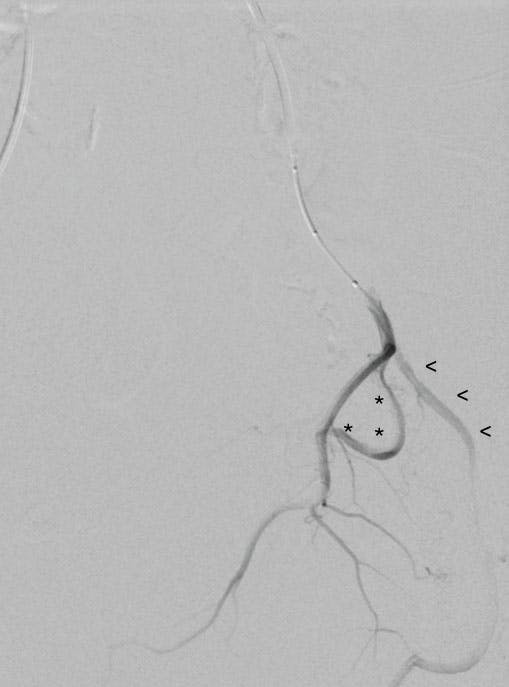

Case Snapshot From Dr. Misono

A man in his early 70s presented with a history of hypertension, hyperlipidemia, diabetes, atherosclerosis, and BPH. He previously underwent transurethral resection of the prostate, which initially helped but is no longer effective. Currently, he urinates up to 30 times daily, about half urgently and often resulting in incontinence. The patient experiences nocturia as well as recurrent episodes of hematuria, sometimes passing up to a cup of bloody urine with clots.

Figure 1. The prostate artery arising from the internal pudendal.

Figure 2. The rectal branch just proximal to the prostate artery—must cannulate past this branch.